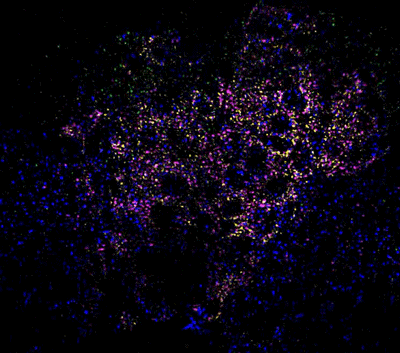

Various populations of chicken neural crest cells.

Various populations of chicken neural crest cells. | Laura Kerosuo and Ceren Pajanoja, NIDCR

Mapping embryonic cell development is exactly what NIDCR investigator Laura Kerosuo, Ph.D., is working on. She studies the behavior of neural crest cells, which form in human embryos around the third week of development. They eventually give rise to the craniofacial skeleton, parts of the salivary glands, teeth, and more. Roughly 20% of human birth anomalies are linked to the neural crest. Understanding the normal timing and migration patterns of these cells can shed light on everything from disorders of the head and face to cancers.